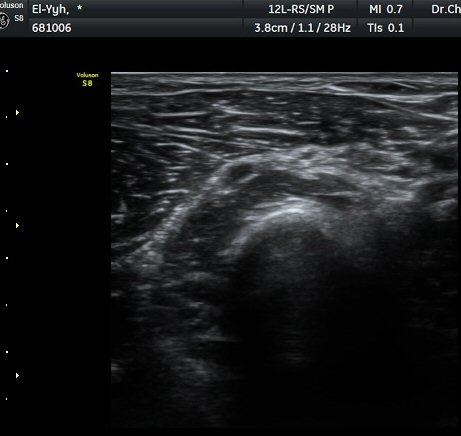

ÃÊÀ½ÆÄ °Ë»ç